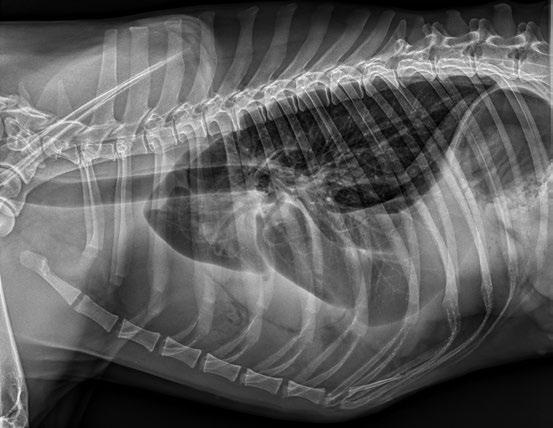

Resolución de quilotórax en un perro con displasia tricúspide